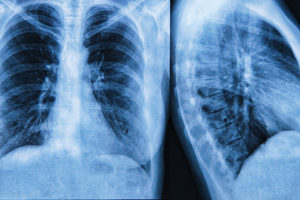

Targeting therapy for lung cancer

Bespoke therapy is a reality for some cancer patients, and its adoption is increasing, including in lung cancer, Gary Culliton reports in his latest Clinical Update.